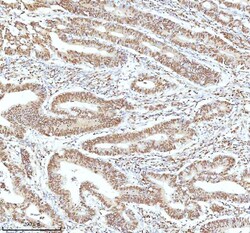

Reconstitute with 0.2 mL of distilled water to yield a concentration of 500 μg/mL. Positive Control - WB: human LNCAP whole cell, human Hela whole cell, human 293T whole cell, human HepG2 whole cell, human Jurkat whole cell, human K562 whole cell, human A549 whole cell, human A431 whole cell. IHC: human bladder cancer tissue, human bladder cancer tissue, human colon adenocarcinoma tissue, human colon adenocarcinoma tissue, human glioblastoma tissue, human glioblastoma tissue, human liver cancer tissue, human liver cancer tissue, human lung adenocarcinoma tissue, human lung adenocarcinoma tissue, human pancreas ductal adenocarcinoma tissue, human pancreas ductal adenocarcinoma tissue, human testicular seminoma tissue, human testicular seminoma tissue. ICC/IF: U2OS cell. Flow: A431 cell. Store at -20°C for one year from date of receipt. After reconstitution, at 4°C for one month. It can also be aliquotted and stored frozen at -20°C for six months. Avoid repeated freeze-thaw cycles.

| Flow Cytometry, Immunohistochemistry (Paraffin), Western Blot, Immunocytochemistry | |